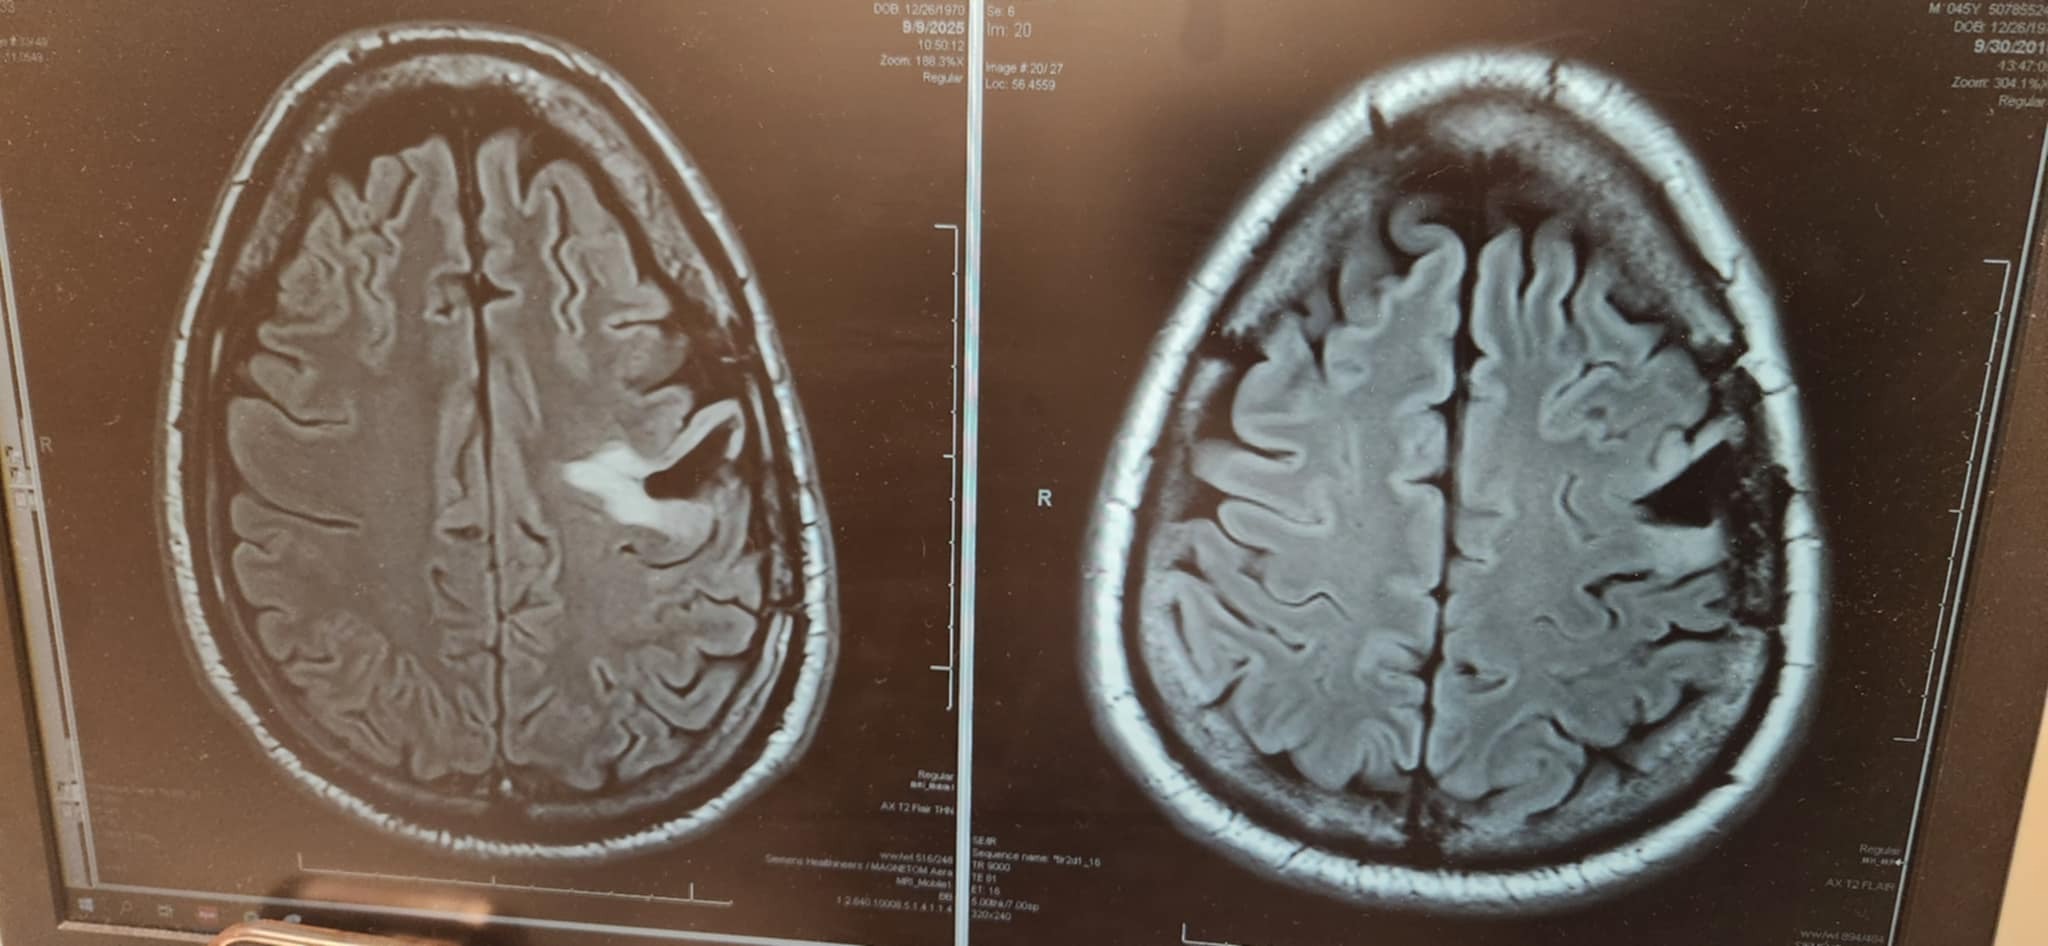

My name is Matt, and I am asking for your help to assist a brother in arms. Christopher (Topher) Barrett is fighting for his life. Ten years ago, he was diagnosed with a brain tumor. He had brain surgery and radiation treatment. After yearly scans, his tumor has returned, and he has to fight again with his brain tumor.